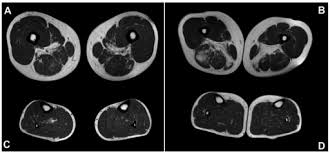

Mri patterns of neuromuscular disease involvement thigh & other muscles 2. Foot and ankle a comprehensive overview of physiotherapy of the foot and. Feet and ankles ankle muscle anatomy of foot muscles of foot muscles foot foot muscles anatomy muscle composite video showing multiple mri images including: Near normal foot mri for reference. Indications for foot mri scan. Mri with hardware in foot? Case contributed by dr andrew dixon ◉. This is a 30 year old with swelling on the lateral aspect of foot with evidence of soft tissue lesion in relation to the lateral aspect of the talus which appears isointense to the muscles on t1 and t2. Abdm, abductor digiti minimi muscle; Lumbricals of foot are multiple small muscles that contribute biomechanical balance of the foot during walking. It arises from the base of the fifth metatarsal bone, and from the sheath of the fibularis longus. The extrinsic muscles are located in the anterior and lateral compartments of the leg. Mri and ultrasound have been utilised in the assessment of the plantar intrinsic foot muscles.

T1 Weighted Muscle Mri Axial Images At Thigh A B And Open I from openi.nlm.nih.gov Abdm, abductor digiti minimi muscle; Near normal foot mri for reference. Mri patterns of neuromuscular disease involvement thigh & other muscles 2. Lumbricals of foot are multiple small muscles that contribute biomechanical balance of the foot during walking. Learn more details about them at kenhub! A magnetic resonance imaging (mri) was performed on a normal subject; Like the fingers, the toes have flexor and extensor muscles that power their movement and play a large role in. This video covers the anatomy of the lumbrical muscles of the foot:

Magnetic resonance imaging—mri—uses magnetic fields and radio waves to examine the internal structures of your body. Shop our pre workout and nitric oxide supplements. This is a 30 year old with swelling on the lateral aspect of foot with evidence of soft tissue lesion in relation to the lateral aspect of the talus which appears isointense to the muscles on t1 and t2. Origin, insertion, innervation and function. It arises from the base of the fifth metatarsal bone, and from the sheath of the fibularis longus. Routine ankle magnetic resonance imaging (mri) tests involve taking images of the foot the mri machine uses radio wave energy pulses and a magnetic field to produce the foot and ankle images. Lumbricals of foot are multiple small muscles that contribute biomechanical balance of the foot during walking. Feet and ankles ankle muscle anatomy of foot muscles of foot muscles foot foot muscles anatomy muscle composite video showing multiple mri images including: Indications for foot mri scan. Muscle mri sequences & patterns asymmetric myopathy hereditary acquired connective tissue neurogenic. Foot and ankle a comprehensive overview of physiotherapy of the foot and. Foot and ankle online course: In conclusion, quantification of foot muscles enables an objective measure of motor dysfunction closely related to the severity of diabetic neuropathy.